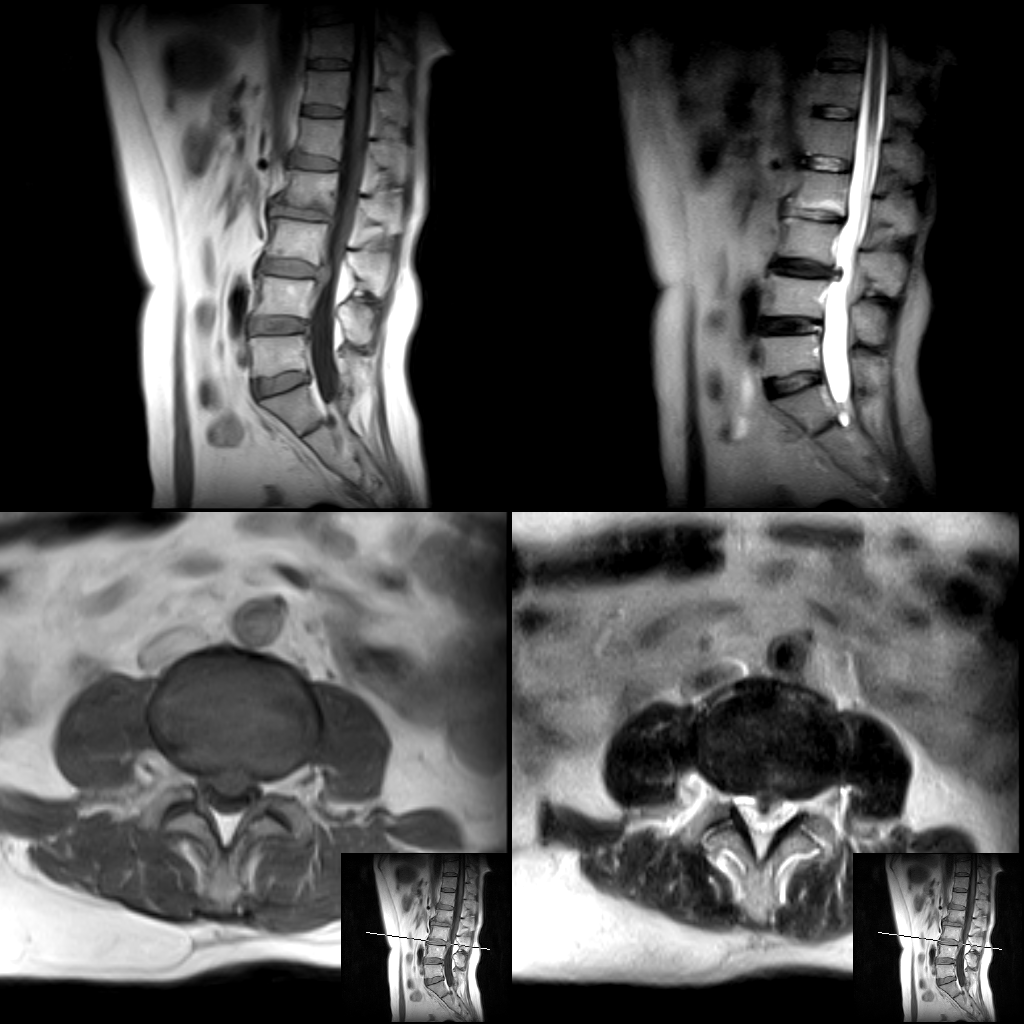

随着医学科学技术的快速发展,磁共振成像(MRI)检查作为一种非侵入性、高分辨率的成像技术,具有广泛的应用范围,已经成为临床诊断中不可或缺的工具。

何军主任以深厚的医学造诣和前瞻性视野,从MRI的基本原理讲起,深入浅出地剖析了磁共振成像的奥秘,检查方法,各类适应症,禁忌症以及最新技术应用等。从理论要点到临床应用,从经典案例到前沿技术,无一不娓娓道来,深刻阐述了MRI技术对于现代临床工作的重大意义。他强调:“MRI以其无创、多参数、高分辨率等独特优势,在中枢神经系统、心血管系统、骨关节及肌肉系统、颈部、腹部、盆腔等病变的诊断中展现出无可替代的价值,希望参与本次培训的医师们能够从中受益,学以致用。”

成都誉美医院骨科现有骨一科、骨二科、中医骨伤科“三驾马车”。诊疗范围包括创伤骨科(上肢、下肢关节骨折,关节周围及骨盆等复杂骨折)、骨关节病(髋、膝关节置换,骨性关节炎、骨质增生等)、脊柱外科(颈椎病、椎间盘突出、椎管狭窄、脊柱侧弯、颈腰椎骨折、椎体滑脱、脊柱脊髓损伤等)、骨病康复(各类骨伤康复、骨关节病康复等)等。尤其在颈椎病、椎间盘突出、骨关节病等方面有深厚的造诣。为不同情况病友提供更加专业且个体化的治疗服务。